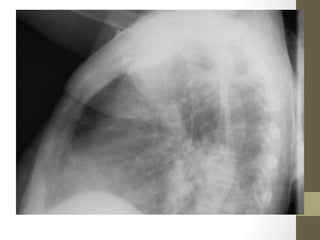

Sigmoid Volvulus

What’s wrong with this picture?

Radiographic Studies: Plain Film •Mostly helpful in ED for: – Free air (suspected perforation) – Pneumatosis (typhlitis) – Dilated loops of bowel with air fluid levels (obstruction) – Foreign body • Free air seen in only 30-50% of bowel perforation